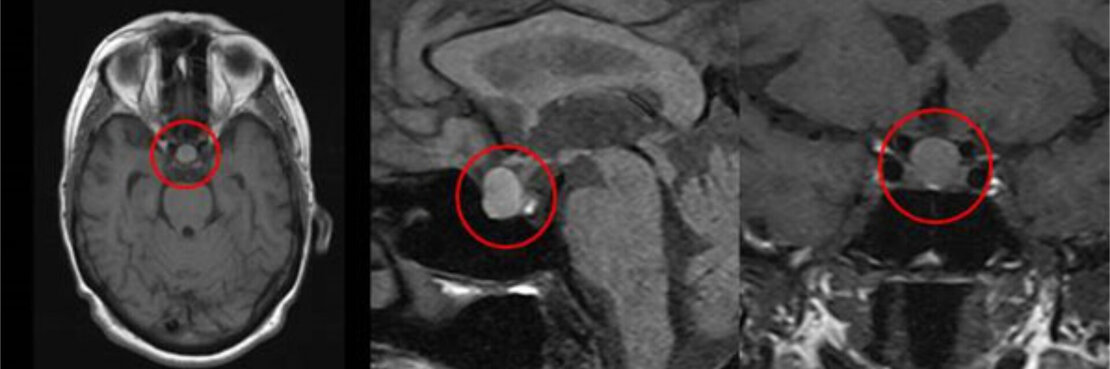

- Magnetresonanztomographie (MRT) der Hypophyse